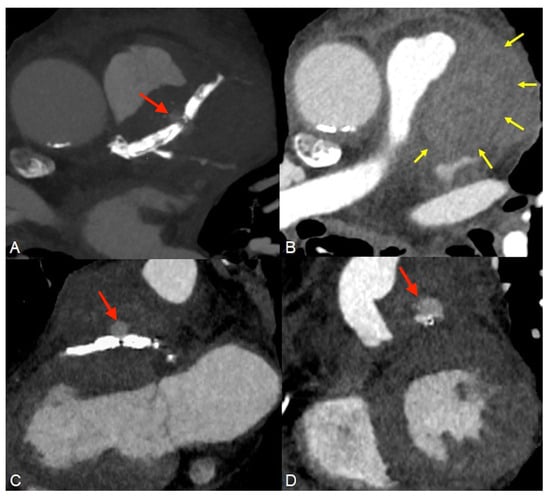

Figure 3. A classic coronary angiography was performed next, where a type IV distal stent fracture involving the proximal LAD stent with dehiscence and slight migration ((A), red arrow) associated with a coronary pseudoaneurysm ((B), yellow arrow) were observed. An attempt was made to install a pharmacologically active post-dilation balloon stent in order to treat the pseudoaneurysm, but without success, which is why the patient was transferred to the cardiovascular surgery ward. The surgical procedure was performed under general anesthesia with orotracheal intubation and extracorporeal circulation, and the final diagnosis was a stent fracture associated with pseudoaneurysm formation and infected pericardial hematoma. Intraoperative view of the complete stent fracture and separation ((C), white arrows). Infected pericardial hematoma ((D), black arrow). The case is atypical, as the stent fracture was type IV (complete transverse fracture of the stent with separation into two fragments and displacement) and occurred at the level of the anterior descending artery. The most common stent fractures reported in the literature involve the right coronary artery, with a more tortuous course, and type III and IV fractures have the lowest incidences [4]. Coronary pseudoaneurysms following stenting are rare complications with an incidence of 0.3–6% and usually arise approximately 6–9 months after the intervention, but cases have been reported earlier than 2 months after the procedure [5]. Unlike similar reports in the literature [6], the attempt to implant a new drug-eluting stent in our patient failed. Finally, surgical revascularization proved to be the appropriate treatment strategy. After removing the pseudoaneurysm and performing an aorto-coronary bypass, the patient showed a favorable recovery and was discharged in a stable condition. Invasive coronary angiography is considered the gold standard for diagnosing intra-stent restenosis, although the invasive nature of the procedure comes with associated risks of mortality and morbidity. Computed tomography angiography (CTA) is a non-invasive imaging technique highly beneficial for follow-up consultations. Coronary artery intrastent restenosis detection has been determined to have high specificity when at least a 64-multislice CT technique is used. CTA can and should also be used when varying symptoms appear after an interventional coronary procedure [7].